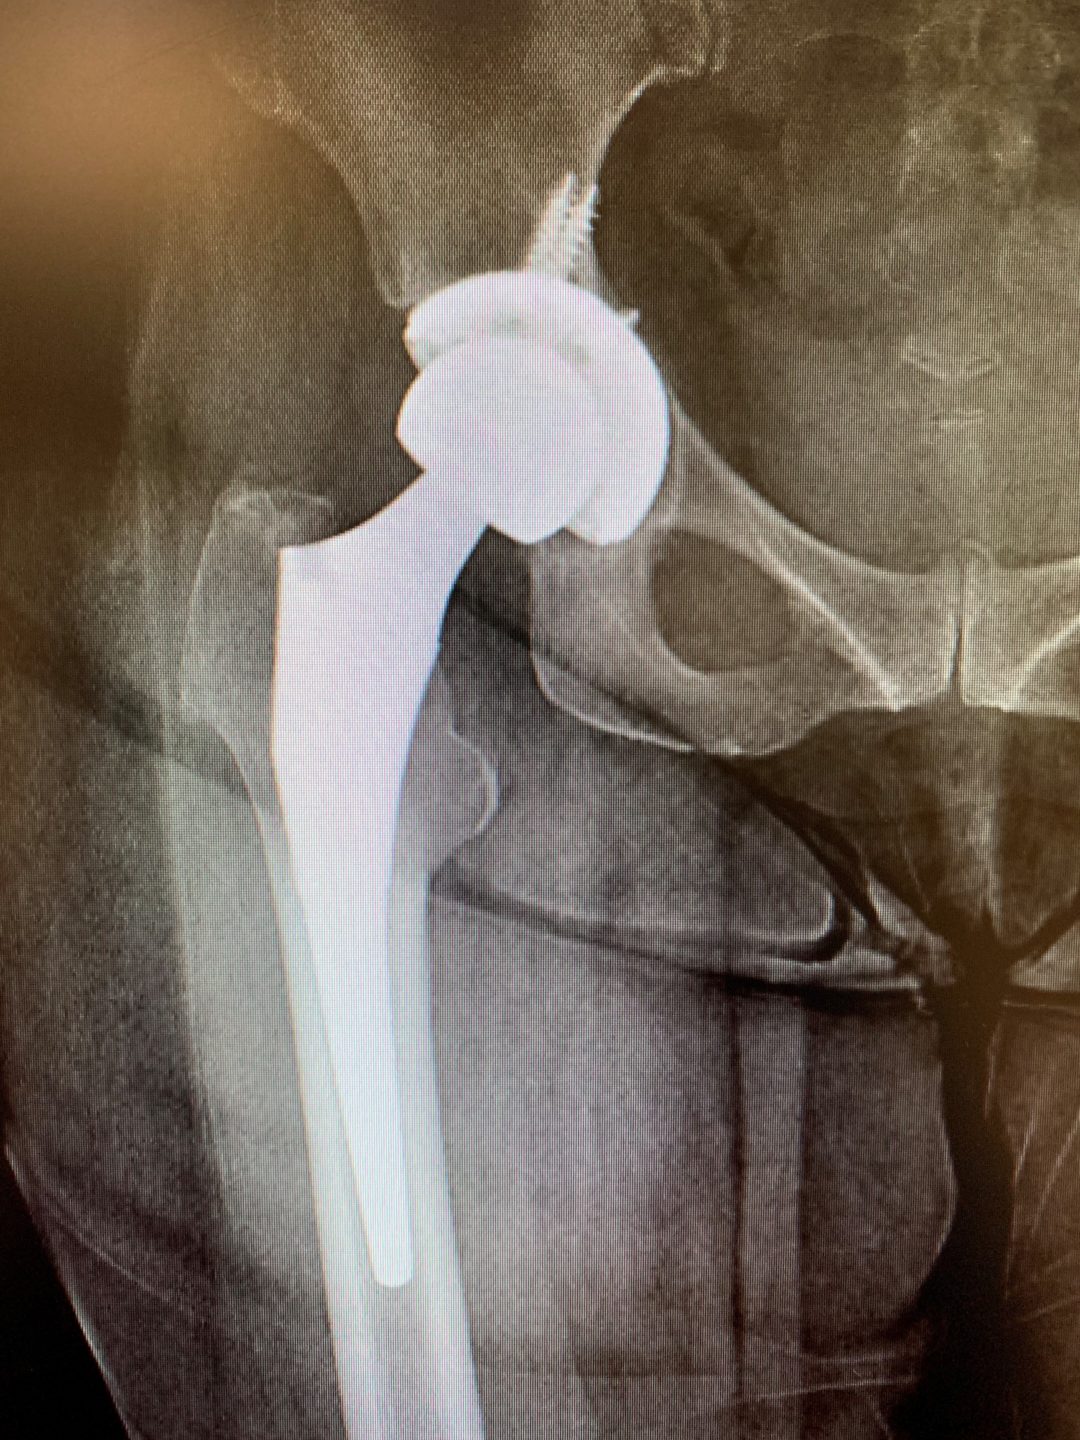

Case Study Revision Total Hip Replacement in a 64year old. Isolated What Is Hip Replacement Revision Surgery What is hip revision surgery? Web revision hip replacement, also known as secondary hip replacement, is needed when your original hip replacement implant fails. It requires extensive planning, as well as the use of specialized. Hip revision surgery is a procedure that repairs or replaces an artificial hip joint. A hip replacement can fail for the following. Web revision hip. What Is Hip Replacement Revision Surgery.